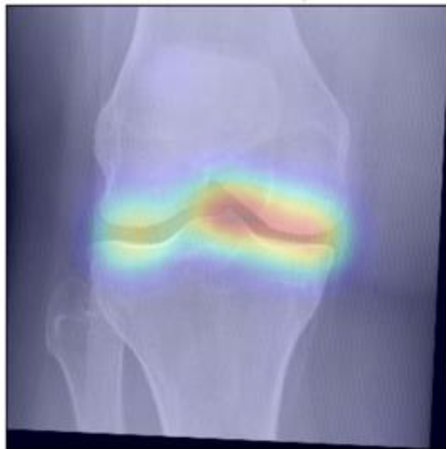

To gain insight into the basis of the CNN’s prediction, we used the GradCAM [24] approach and visualized the attention maps for the well-predicted knees. Examples of attention maps are presented in Figure 5. We observed that in various cases, the CNN paid attention to the compartment opposite to the one where degenerative change became visible during the follow-up visits. Additional examples of such attention maps are presented in Supplementary Figures 3, 4, 5 and 6.

Refer to caption

(a)

(b)

(c)

(d)

Figure 5: Examples of attention maps for progression cases and the corresponding visualization of progression derived using follow-up images from MOST datasets. Here, subplots (a) and (c) show the attention maps derived using a GradCAM approach. Subplots (b) and (d) show the joint-space areas from all the follow-up images (baseline to 84 months). Here, the subplot (b) corresponds to the attention map a) and the subplot (d) corresponds to the attention map (c).